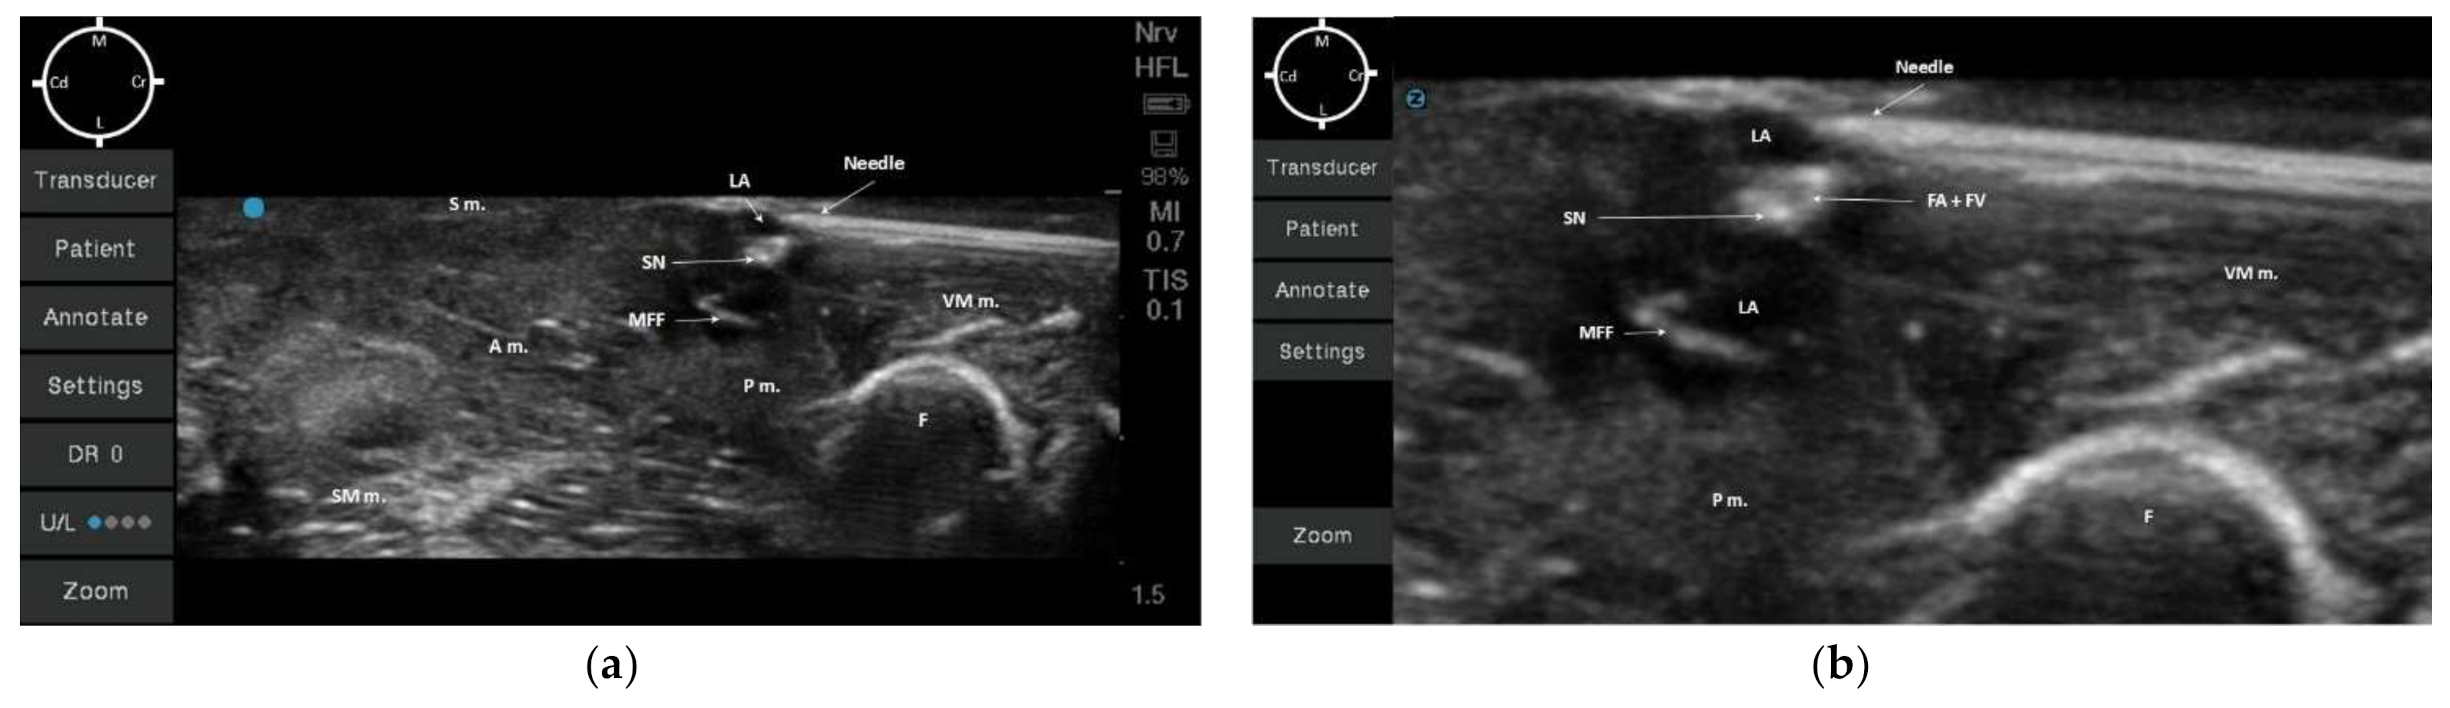

2.2. Sono-Anatomy Study and US-Guided Saphenous Nerve Block Design

3.2. Sono-Anatomy Study and US-Guided Saphenous Nerve Block